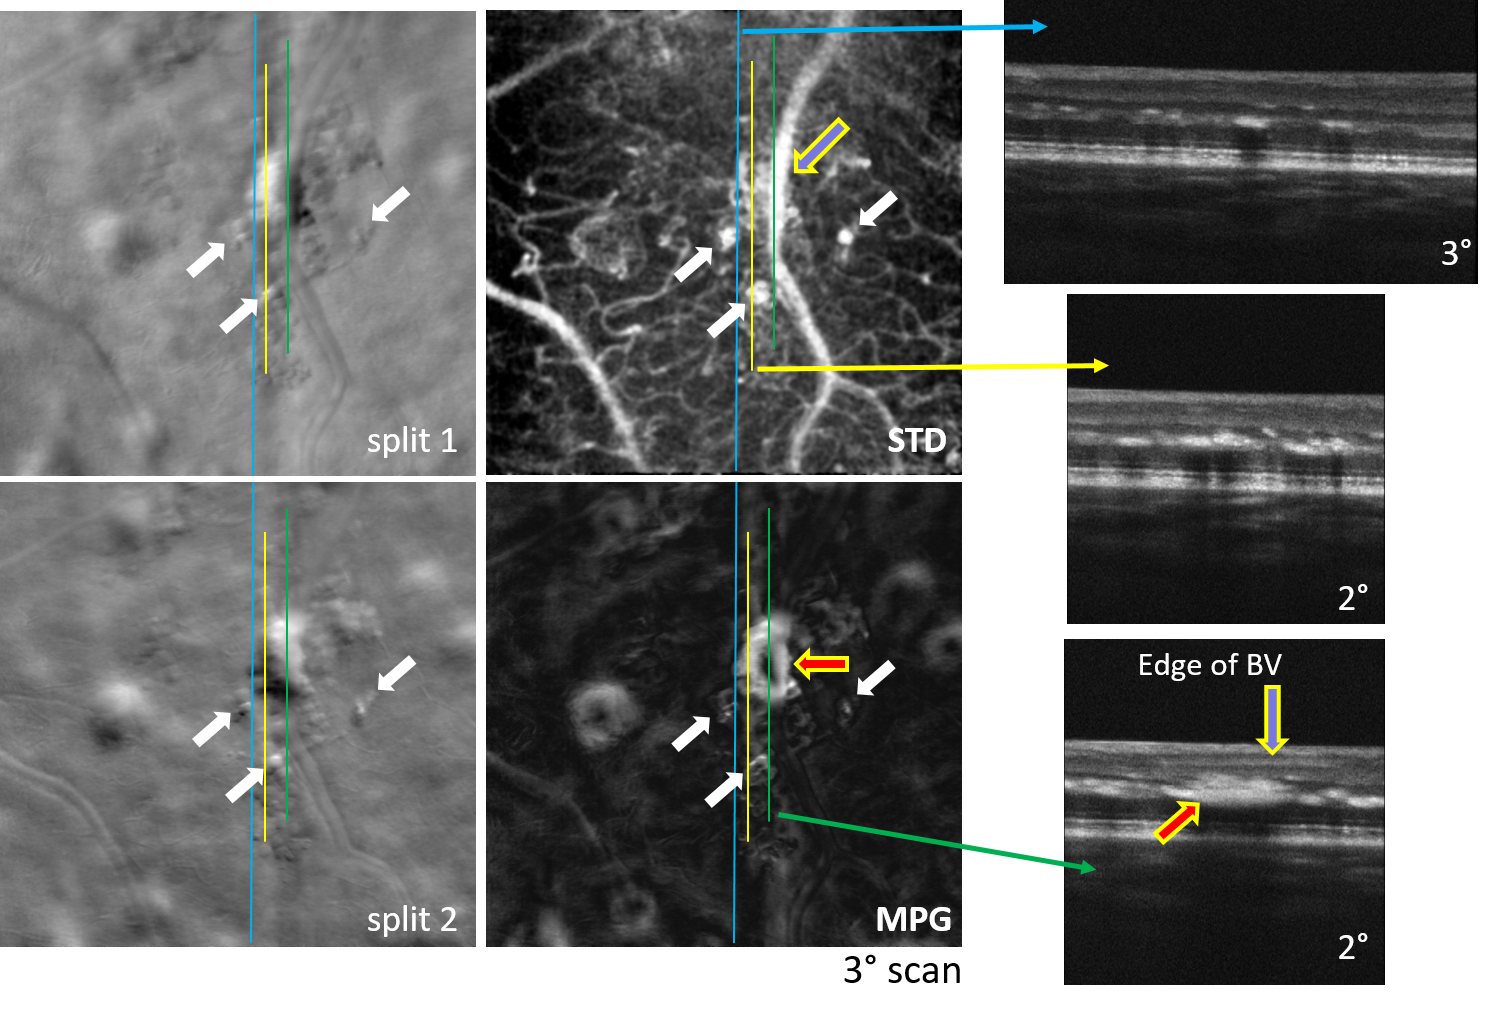

Simultaneous AO-SLO and AO-OCT

Motion Contrast, Phase Gradient, and Simultaneous OCT Images Assist in the Interpretation of Dark-Field Images in Eyes with Retinal Pathology”, Diagnostics, 14(2), 184, (2024)